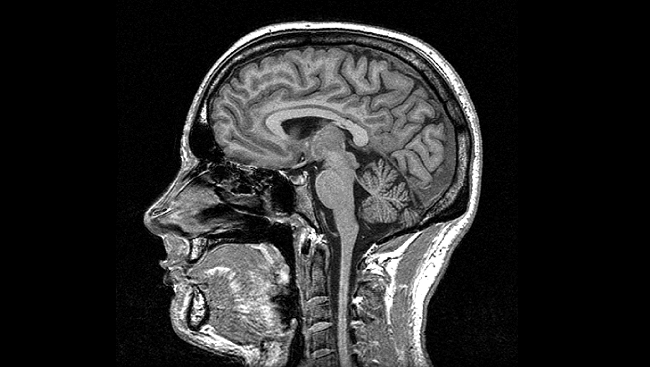

O součastnosti i budoucnosti neurochirurgie při léčbě onemocnění bude v pátek hovořit i profesor Vladimír Beneš z Neurochirurgické kliniky 1. LF UK a ÚVN v Praze. Zaměří se především na neurotransplantace, neuroprotézy a neuromodulace. O tom, „jak se dívá do mozku“, bude mluvit Ondřej Novák z Ústavu fyziologie 2. lékařské fakulty UK. Ke studiu mozku ve zdraví a nemoci používá nejmodernější metody měření aktivity a ovládání jednotlivých neuronů v mozku pomocí světla – optogenetiku a optofyziologii.